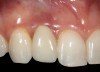

It was determined that additional augmentation was required to increase the soft-tissue volume, so a subepithelial connective tissue graft was acquired from the palate (Figure 8),23,24 placed, and allowed to mature for at least 3 months. Second-stage implant undercovering surgery with a palatal-biased incision was performed after tissue maturation to further thicken the labial soft tissues. In addition, a flat contoured healing abutment was placed to allow the soft tissues to mature without risk of recession, and the RBR replaced (Figure 9). After 4 to 6 weeks of healing, a flat contoured screw-retained provisional restoration was inserted (Figure 10) with the proper submergence profile to restoratively sculpt the soft tissues. An implant-level impression was made and the definitive cement-retained metal-ceramic restoration fabricated and inserted (Figure 11 through Figure 13). The final esthetic outcome to restore the proper length and proportion of the right lateral incisor to match that of the contralateral incisor was accomplished using the treatment steps outlined above, where the mucosal tissues were augmented after implant decoronation (Figure 14).

Fig 14. The extraoral smile view of the esthetically satisfied patient at 4 years recall.